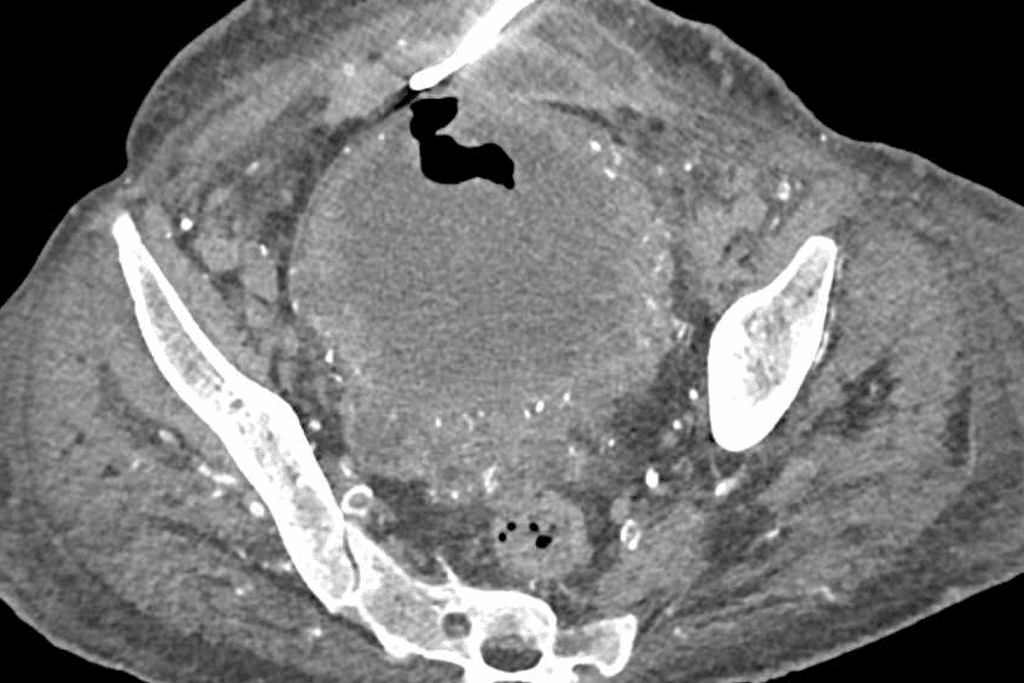

• Periodic imaging tests, such as CT scans or MRIs